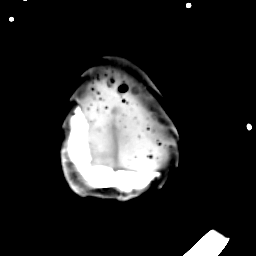

Meningioma: Roentgen-ray CT #2 -- Slice #21

[Home][Help][Clinical] Slice 21